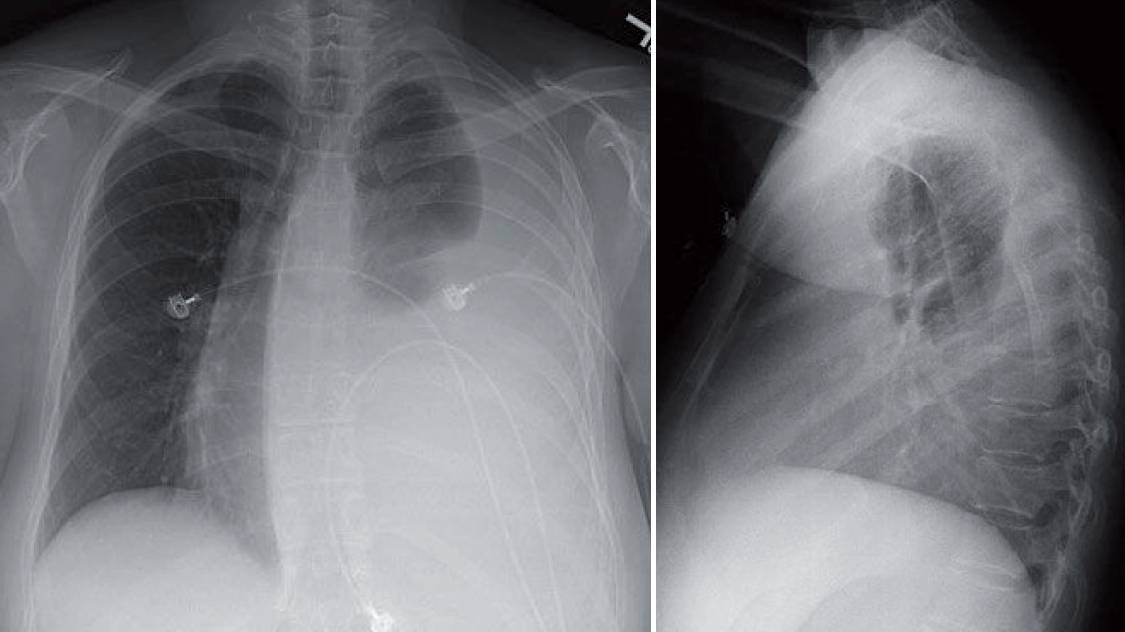

42-year-old woman with shortness of breath receives this chest radiograph.

What’s the diagnosis ?